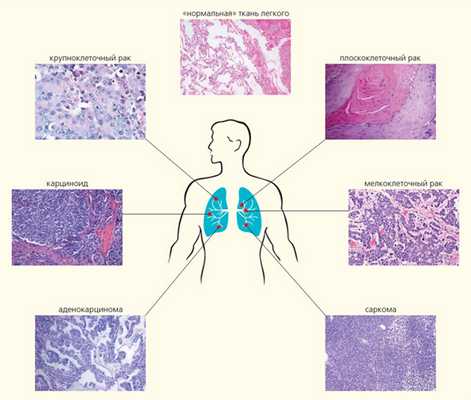

Помимо установления самого факта злокачественной трансформации для назначения индивидуализированной терапевтической схемы важно как можно раньше определить гистологический тип опухоли и оценить стандартные маркеры агрессивности (степень дифференцировки, митотическая активность и т. д.). В пределах одного органа патологический процесс может развиваться по совершенно разным сценариям, вовлекать разнообразные клетки и структуры. Например, среди злокачественных новообразований легкого насчитывают, по современным представлениям, более шести гистологических типов, для каждого из которых необходимы свои терапевтические подходы (рис. 2) [1]. Мелкоклеточный рак легкого отличается стремительным течением, ранним метастазированием и очень плохим прогнозом. Карциноидные опухоли, происходящие из клеток диффузной нейроэндокринной системы, имеют наилучший прогноз; это единственный тип карцином легкого, который, как ныне считается, никак не связан с курением. Саркома легких — агрессивная опухоль, развившаяся из клеток соединительнотканных структур легкого. Аденокарциномы состоят преимущественно из железистых клеток и имеют периферическую локализацию. Опухоли этого типа зачастую развиваются у некурящих людей. Они могут нести активирующие мутации в генах EGFR, ALK и ROS1, которые являются терапевтической мишенью для действия таргетных препаратов — ингибиторов тирозинкиназ.

Рис. 2. Гистологические типы рака легкого: мелкоклеточный рак (14%); плоскоклеточный (эпидермоидный) рак (20%); аденокарцинома (38%); крупноклеточный рак (3%); карциноид (5%); мезенхимальные, в том числе саркомы и лимфомы (5%); опухоли смешанных типов — плоскоклеточный и аденокарцинома, аденокарцинома и мелкоклеточный и т.д. (15%)